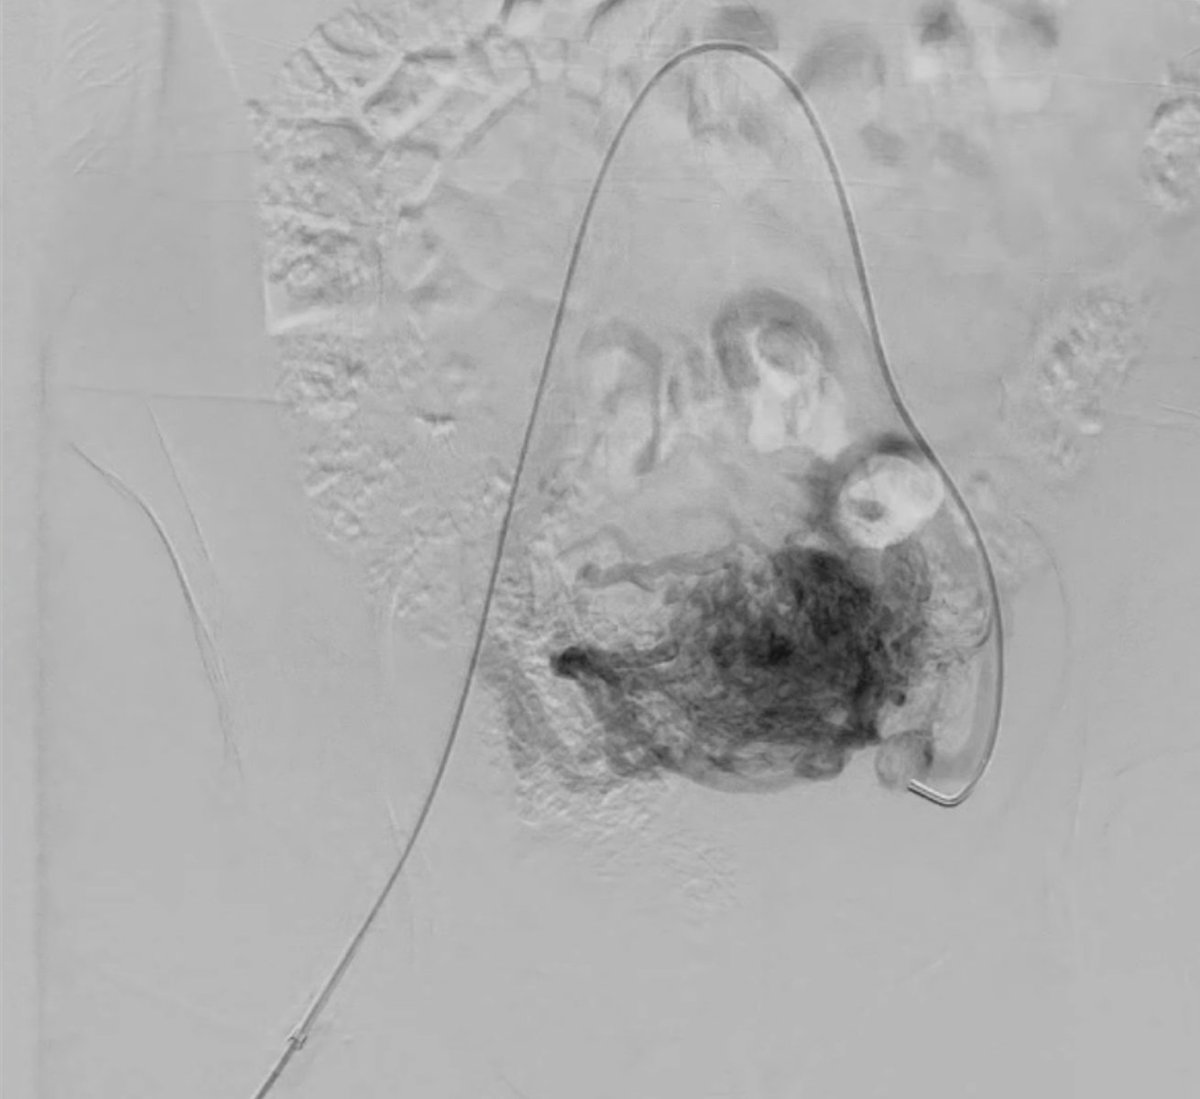

#𝐓𝐫𝐚𝐢𝐧𝐞𝐞𝐓𝐡𝐮𝐫𝐬𝐝𝐚𝐲 — 𝐢𝐧𝐯𝐞𝐬𝐭𝐢𝐧𝐠 𝐢𝐧 𝐭𝐡𝐞 𝐟𝐮𝐭𝐮𝐫𝐞 𝐨𝐟 𝐈𝐧𝐭𝐞𝐫𝐯𝐞𝐧𝐭𝐢𝐨𝐧𝐚𝐥 𝐑𝐚𝐝𝐢𝐨𝐥𝐨𝐠𝐲

📢 Join us at the Ask me anything: an MDT approach to patient care session and learn how expert IRs dealt with the challenging #IO cases. ➡️ Visit #ECIO2026 website and learn more about the congress programme: bit.ly/4lhZk7m